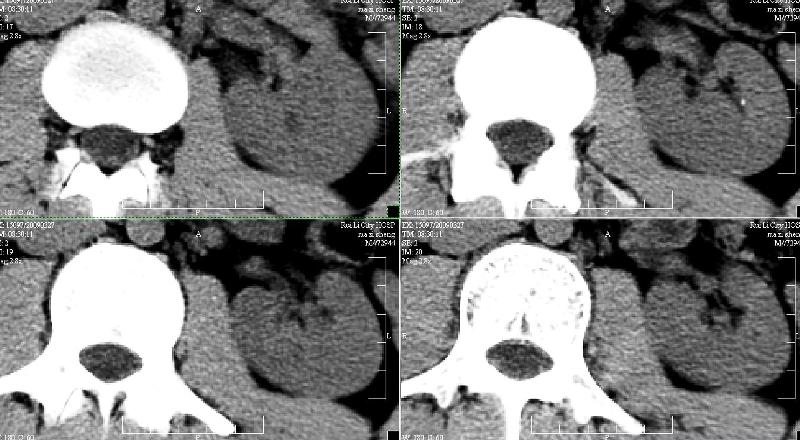

标题: CT19133:M,28岁。 [打印本页]

标题: CT19133:M,28岁。

ct发现左肾小结石而右侧腰部疼痛?右肾是伸入实质的肾盏吗?